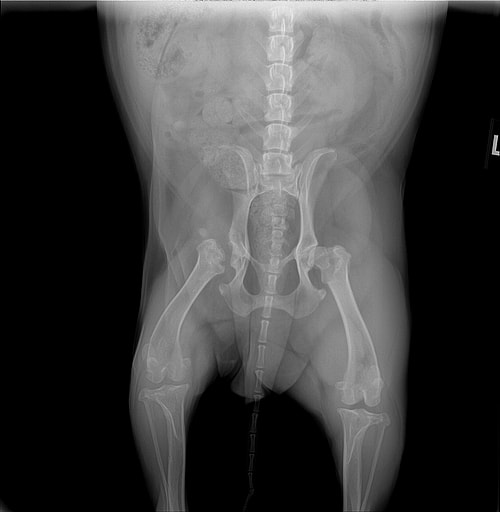

>She recently had hip surgery 2 months ago and was having trouble walking on that leg.

>Will most likely need knee double surgery and some dental work down the road once she was more stabilized.